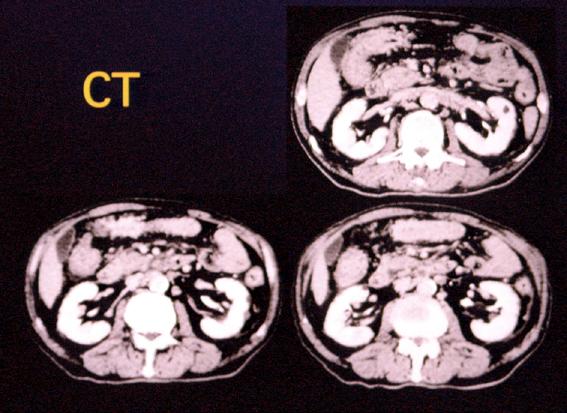

clasificación del pacienteLesión que asemeja tumoración/infiltración desde órganos contíguos

parte(separada por órganos)estómago(región)/mas de dos

método de exámenTAC

diámetro mayor del tumor40 -